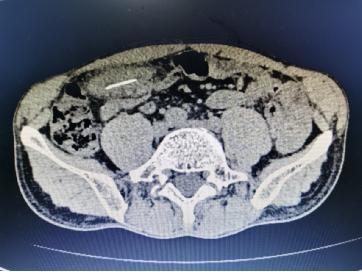

CT检查可见胡先生体内有异物 。

接诊的急诊科医生安排胡先生做检查 , 结果显示血液中白细胞明显升高 , 腹部CT更进一步提示 , 腹腔内有异物 , 伴有脓肿形成 。 随后 , 胡先生被收住到血管小儿胃肠二外科 。 值班医生刘俊仔细查看腹部CT检查结果 , 发现病灶处是个长约3厘米的异物 , 推断是异物引发的消化道穿孔 , 立即安排胡先生接受腹腔镜探查 。